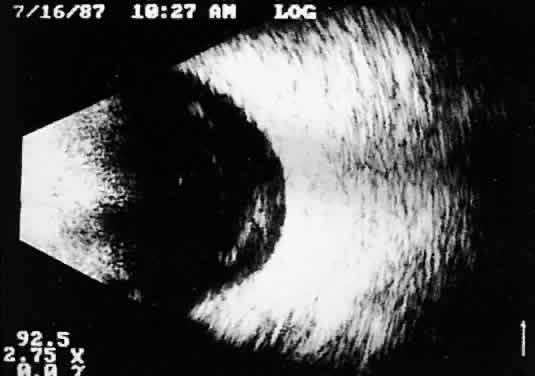

Recent improvements in image quality and fused, real-time display have made ultrasound image interpretation easier for every ultrasonographer. Visualization of subtle changes such as movement and recognition of the posterior formed vitreous hyaloid are now possible, even in clear media situations. These clear vitreous structures, which are often exceedingly difficult to appreciate optically, can be recognized ultrasonically after a relatively short period of training (Fig. 17). Clinically, establishing the position of the posterior hyaloid is important in evaluating a variety of vitreous retinal disorders, such as macular holes, tractional detachments, and partial or complete vitreous separations.16,17

Fig. 17. Contact B-scan: posterior formed vitreous face separation, with prominent Weiss ring evident.